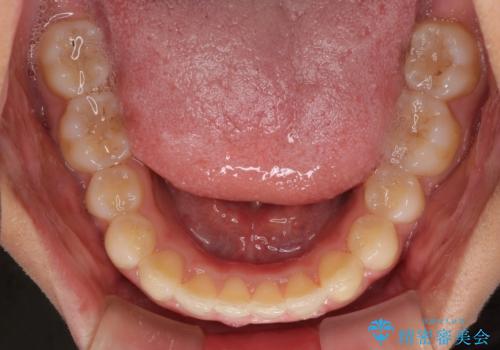

- 深い咬み合わせ(ディープバイト)と前歯のデコボコを気にして来院された患者様です。

インビザラインによる上下歯列の側方拡大と後方移動、IPR(歯と歯の間を削る)にるスペースの獲得により、デコボコとディープバイトを改善することとしました。

1日22時間の装着時間をしっかり守ってくださったので、予定通り1年で治療を終えることができました。

ディープバイトによる食いしばり癖も解消され、患者様には大変満足していただきました。